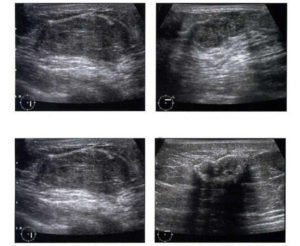

Лечение новообразований может быть консервативным и оперативным. Однородные анэхогенные округлые множественные новообразования (мастопатия) могут лечиться консервативно:

Новообразования с низким риском озлокачествления, небольшого размера, не склонные к росту могут просто наблюдаться. Включения с высоким риском малигнизации, быстро растущие или крупные — удаляются оперативно. После операции обязательно проводить контрольные обследования УЗИ. Женщины должны находиться на учете у маммолога.

Метастатические опухоли в грудной железе могут быть единичными, но намного чаще множественными. Они могут пальпироваться или нет. Поражение может быть односторонним или двусторонним, с вовлечением лимфатических узлов или без него.

При ультразвуковой маммографии определяется образование неоднородной структуры, гипоэхогенное, округлой формы с довольно ровными и четкими контурами. Появление гиперэхогенной капсулы (участков десмоплазии) на УЗИ молочной железы нетипично.

Как правило метастазы, в отличие от первичных опухолей, зачастую располагаются в подкожной зоне. Метастазы могут быть основным ультразвуковым проявлением онкологического заболевания у пациентки без первично выявленного очага или регистируются в грудной железе на поздних стадиях заболевания.